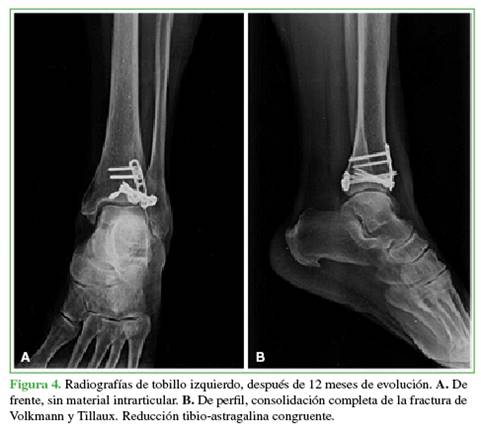

Después de 12 meses, se documentó la consolidación de las fracturas (Figuras 4 y 5), y la paciente reanudó sus actividades habituales; el puntaje de la American Orthopaedic Foot and Ankle Society era de 91 y el de la escala funcional de Olerud-Molander de 95 (Figura 6).